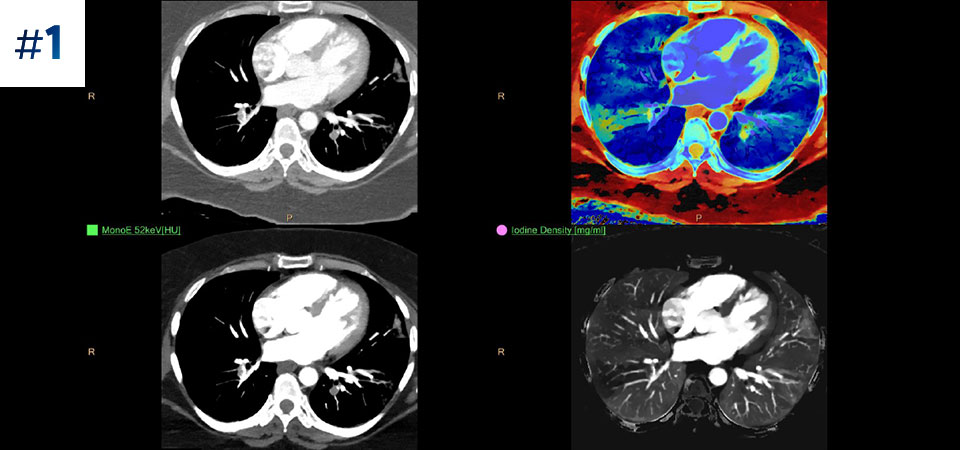

Грудная клетка, исследование на перикардиальный выпот